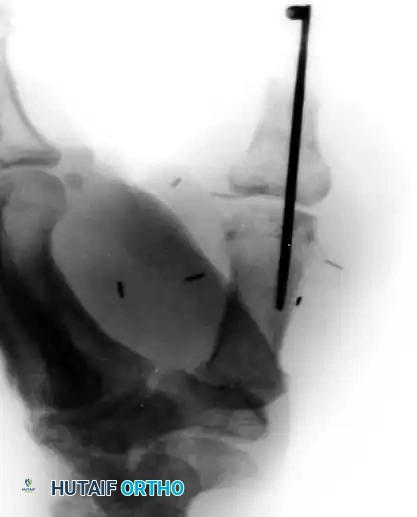

Step 4: Radiographic Confirmation

Postoperative imaging is critical to ensure proper alignment and bony apposition between the transferred phalanx and the host metacarpal.

Image

Figure 14-1E: Radiographic appearance demonstrating the transfer of the middle finger proximal phalanx to the thumb metacarpal, stabilized by a single longitudinal K-wire.